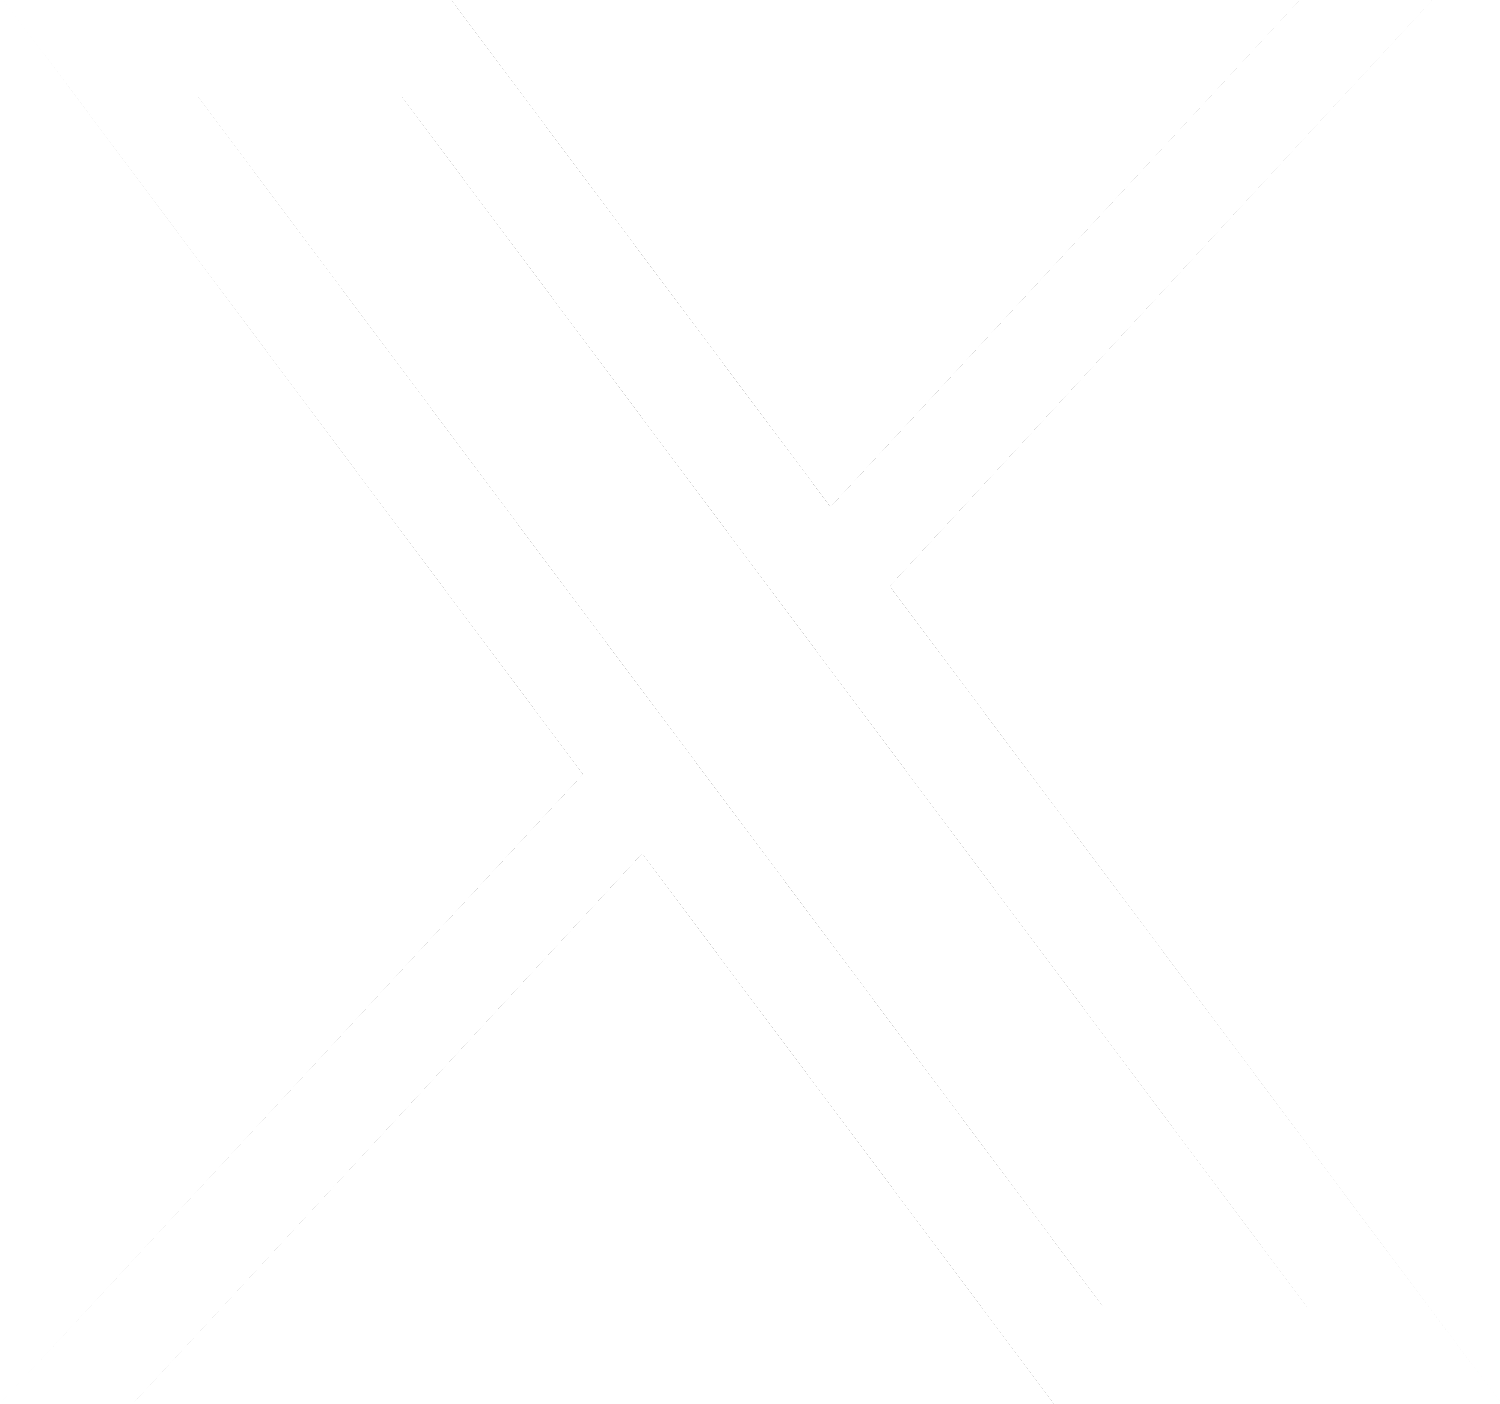

Los rápidos resultados de Paulo los compartió en su cuenta de Instagram con estas sorprendentes imágenes en las que se observan cómo los tumores que tenía alrededor de su cuerpo en la primera imagen, desaparecen en la segunda imagen.

Ahora su cuerpo está limpio y logró la remisión total de su linfoma. Las imágenes las acompañó de un emotivo texto en el que confiesa que fueron años difíciles y relata lo que vivió con su enfermedad y en el hospital.

“En abril de 2018 estaba en quimioterapia. Era mi segundo cáncer y mi primer linfoma; no tenía idea de que habría dos más por venir. Fueron 1.800 días, decenas de sesiones de quimioterapia y pruebas de imagen, hospitalizaciones, trasplantes de médula ósea, cuatro biopsias, covid, sangrados, UCI… Incluso, los médicos consideraron un milagro que saliera vivo de la hospitalización y la cirugía. Ahora, en 2023, las imágenes del antes y después no dejan lugar a dudas: ¡Remisión completa de mi tercer linfoma! Es el éxito de Cart T Cell”.